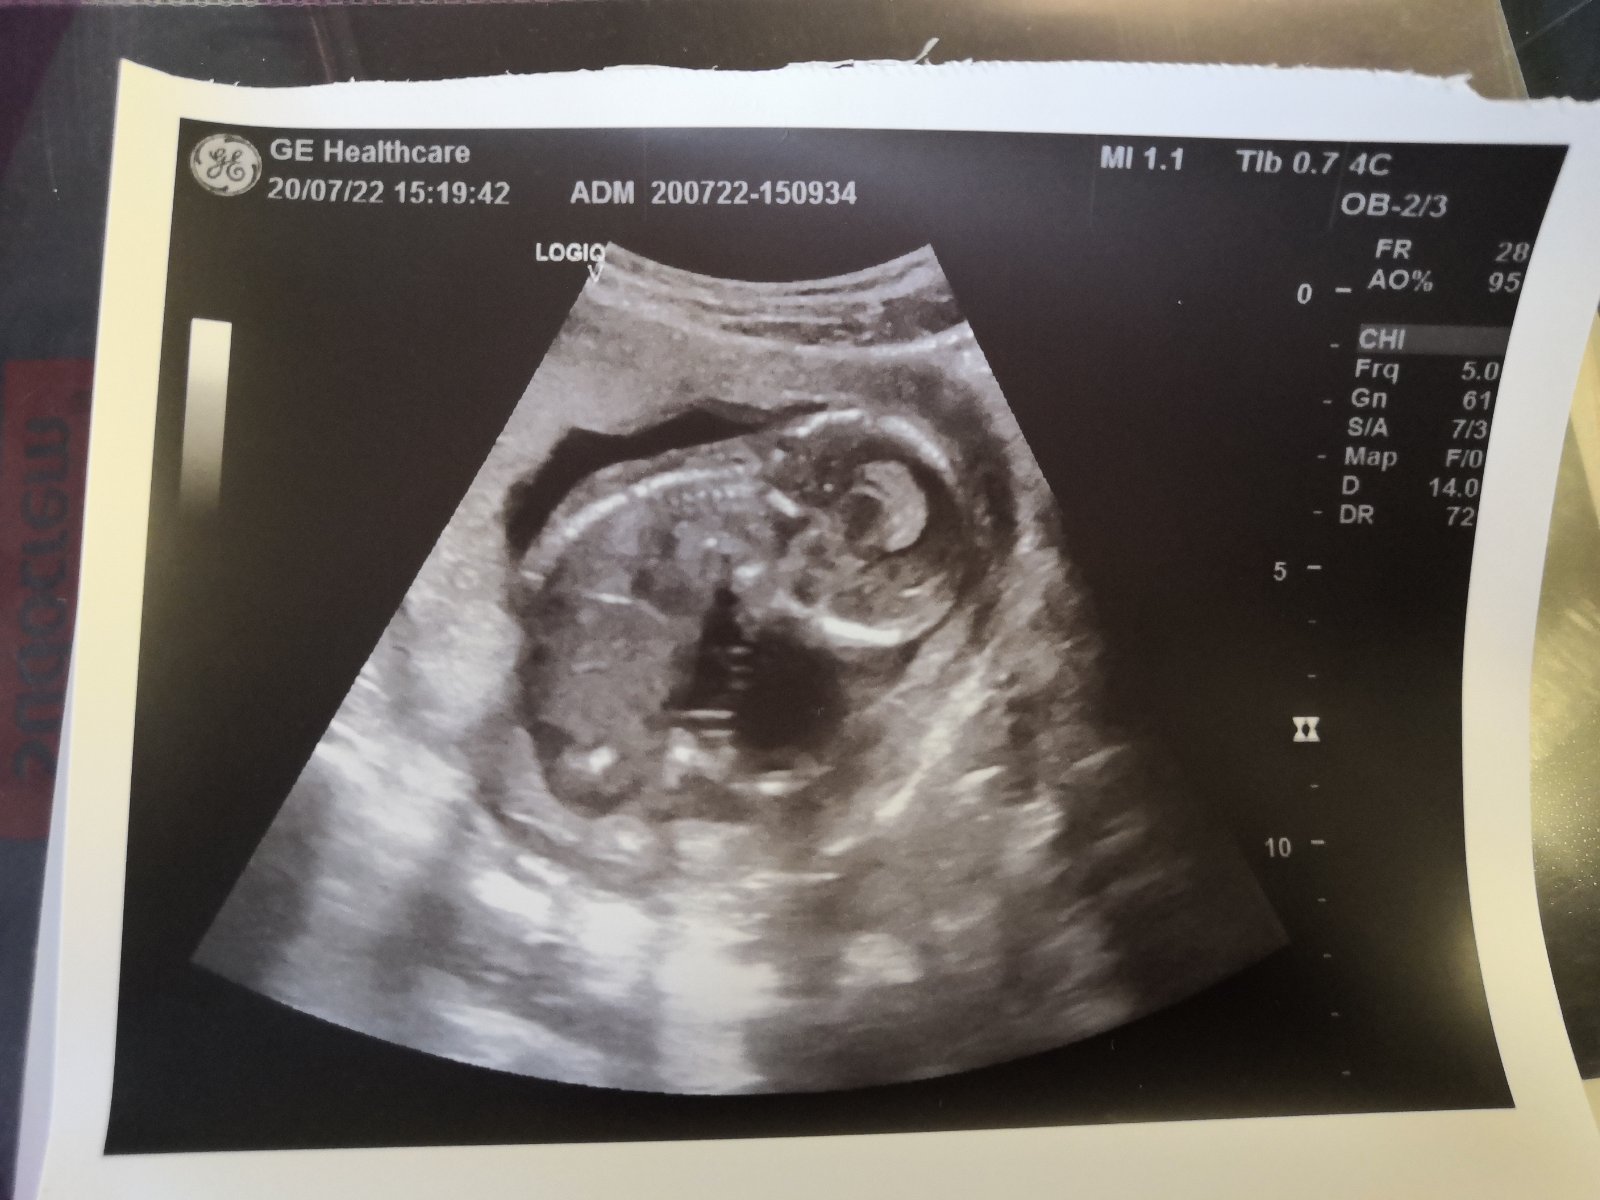

Ahoj holky, dá se z této fotky vyčíst velikost plodu? Bohužel jsem se na to doktorky zapomněla zeptat. Dnes jsem 16+1tt.

Byla by to hodnota CRL a tu tam nevidim. Jedine jestli to nemas ve zprave.

@lentilkah oprava, tak to mám napsáno v průkazce, velikostně jsem 16+3. ☺️